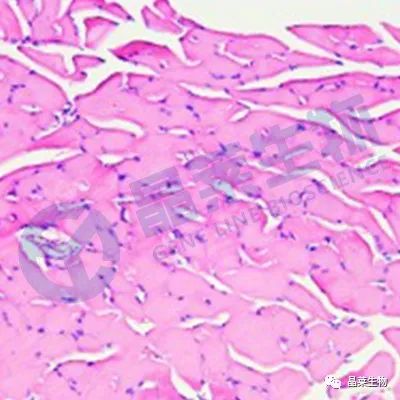

1. HE染色

应用:HE染色是最常用的组织学染色方法,可以用于观察组织结构、细胞形态和核染色质等。可用于病理诊断、评估组织损伤程度以及确定肿瘤类型等。

结果判断:细胞核呈蓝色或紫色,细胞质和其他组织结构呈粉红色。

样本检测:固定的组织切片,如肿瘤组织、器官组织等。

优缺点:简单易行,可以提供关于细胞形态学和组织结构的信息。缺点是不能提供特定蛋白质或分子的信息。